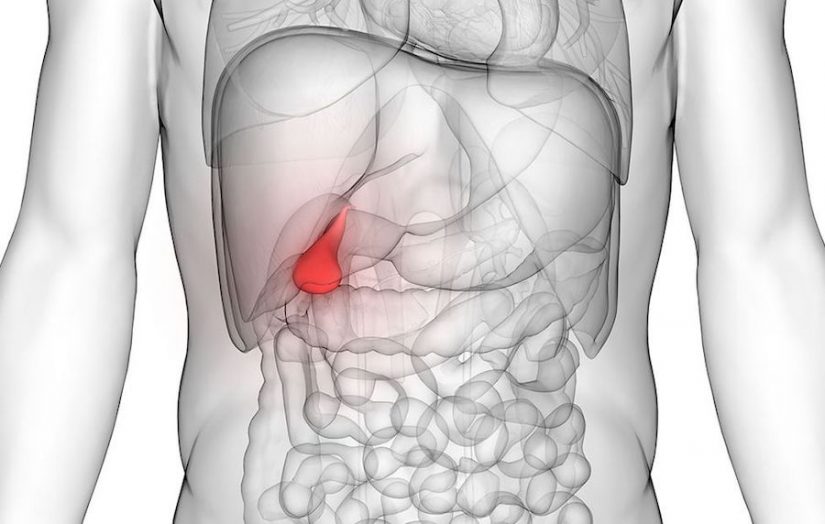

Você sabe o que é e o que faz uma vesícula biliar?

O órgão em forma de pêra, que fica pendurado no fígado e no pâncreas, atua como uma instalação de armazenamento para a bile, liberando-a nos intestinos regularmente para ajudar o corpo a digerir as gorduras.

Muita gente nem imagina, mas uma vesícula biliar defeituosa pode causar sérios problemas – geralmente, na forma de cálculos biliares, também conhecidos como pedra na vesícula.

Os cálculos biliares são a formação de cálculos no interior da vesícula biliar (em 90% dos casos) ou dos dutos biliares (dentro e fora do fígado).